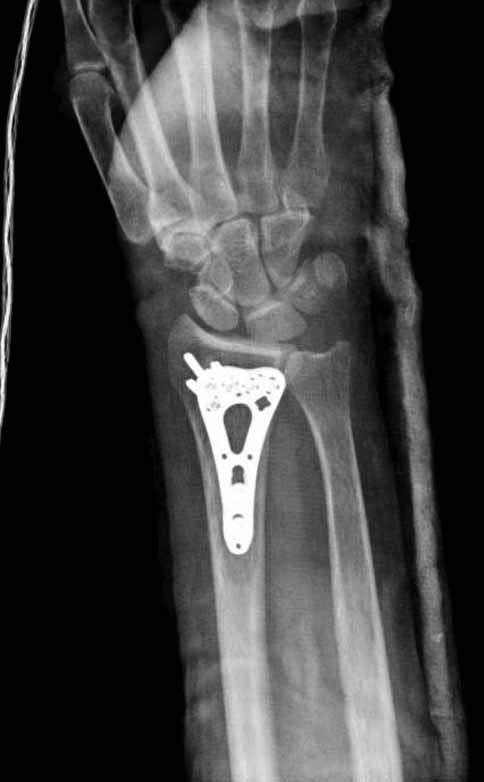

Стандартная волярная пластина для дистального отдела лучевой кости (Synthes; Stryker; Chm; Рыбинск;ЦИТО;Остеомед,De puy; Intercus GmbH)

Лучше с угловой стабильностью.

Хорошие волярные (ладонные) пластины предмоделированны и репозиция происходит на пластине.

Стандартный ладонный (волярный) доступ.

К сожалению аналогичную картинку у оперированной больной не нашел (хотя и копировал- бардак в компе). Там поставили волярную пластинку ChM, которую закупила больница.

Сегодня все компании: Synthes, Stryker, Zimmer, Acumed, TriMed и т.д. имеют пластины для фиксации дистального перелома лучевой кости. На снимке метод фиксации дистальных переломов, справа Stryker, а слева пластина Synthes,

женщина 58 лет, политравма.